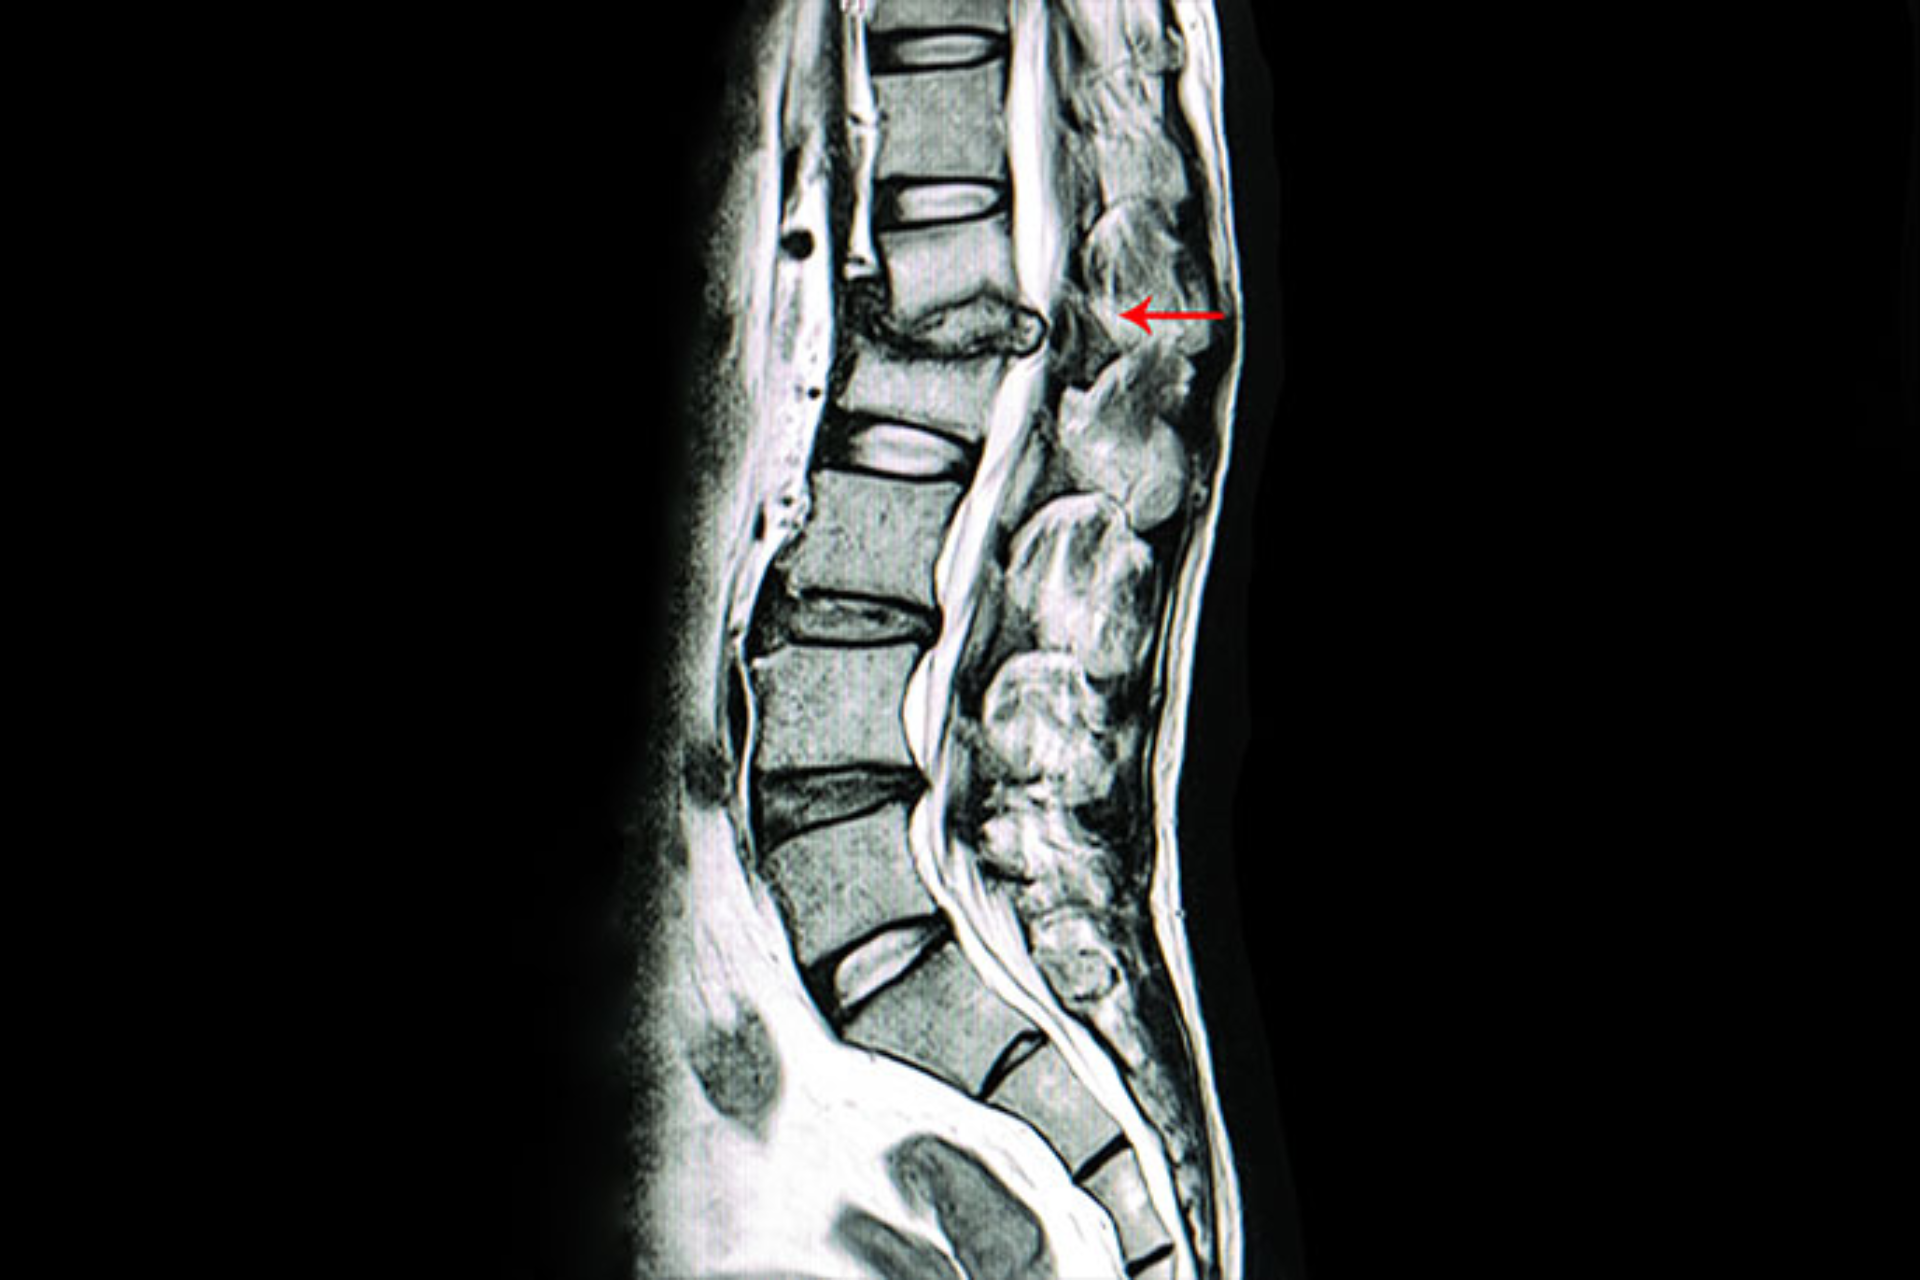

Though TB commonly affects the lungs, it can also affect bones and joints (called skeletal tuberculosis).

In fact, the spine is the most common site of bone TB. Get the best tuberculosis spine treatment in Vizag from Dr. B. Leela Prasad.